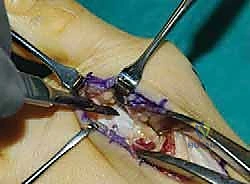

يقوم الدكتور هطيف بعمل شق جراحي دقيق على الجانب الداخلي أو العلوي لمنتصف القدم للوصول إلى المفصل الرسغي المشطي الأول (TMT joint). يُراعى في الشق الجراحي الحفاظ على الأنسجة الرخوة والأعصاب والأوتار المحيطة باستخدام تقنيات الجراحة الدقيقة.

3. إعداد المفصل (Joint Preparation)

هذه هي الخطوة الأكثر دقة. باستخدام أدوات جراحية دقيقة، يتم إزالة الغضروف المفصلي بالكامل من قاعدة عظم المشط الأول ومقدمة العظم الإسفيني الإنسي. يجب إزالة الغضروف وصولاً إلى العظم الإسفنجي السليم الغني بالدم لضمان التحام العظام (Fusion) لاحقاً.

4. التصحيح وإعادة المحاذاة (Correction and Realignment)

بمجرد إعداد السطوح العظمية، يقوم الدكتور هطيف بإعادة توجيه عظم المشط الأول. يتم دفعه نحو عظم المشط الثاني لتقليل الزاوية (IMA)، وتدويره لتصحيح الدوران، وخفضه للأسفل لتصحيح المستوى السهمي. هذا يصحح التشوه بالكامل من قاعدته. يتم استخدام أسلاك كيرشنر (K-wires) مؤقتة لتثبيت العظام في الوضع الجديد والمثالي. يتم التأكد من التصحيح باستخدام جهاز الأشعة السينية الفلوري (C-arm) داخل غرفة العمليات.

5. التثبيت الداخلي (Internal Fixation)

بعد التأكد من المحاذاة المثالية، يتم تثبيت العظام بشكل دائم. يستخدم الأستاذ الدكتور محمد هطيف أحدث التقنيات العالمية في التثبيت، والتي تشمل عادة مسامير تيتانيوم متقاطعة (Crossed Screws) أو شريحة معدنية متخصصة مع مسامير (Plating System) لضمان أقصى درجات الثبات والضغط بين العظمتين، مما يسرع من عملية الالتئام.